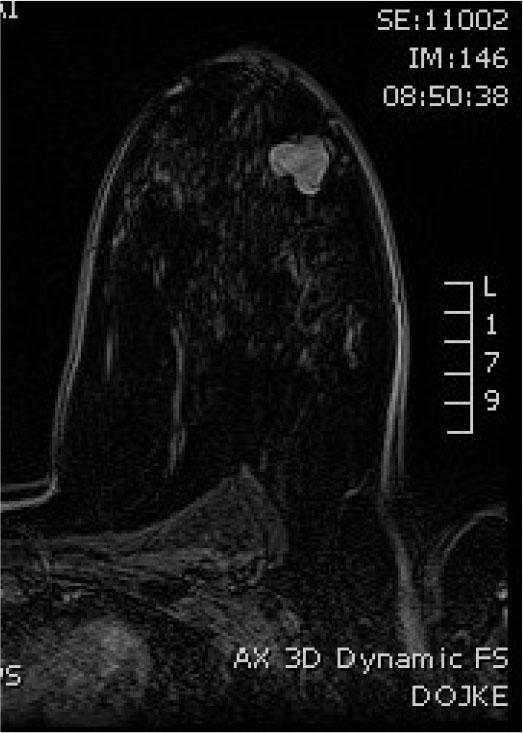

Axial MRI T2W section showing heterointense tumor mass

The review was supplemented by MRI examination, which showed retro and paramamilar tumor mass, in the lower outer quadrant, mixed signal intensity (SI) in T2W / STIR sequences, decreased SI in T1W sequence, postcontrast elevated SI, dynamic characteristics of rapid “wash in”, with a curve of plateau type with few oval shaped lymph up to 10 mm, classified as BIRADS 4 (Figures 2,3,4). Differential diagnostic could correspond to fibroadenoma or fibroadenoma like lesions (FA like lesion). CNB was performed under ultrasound control under local anesthesia and three samples were taken.